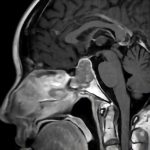

断層撮影

手術前1

手術前2